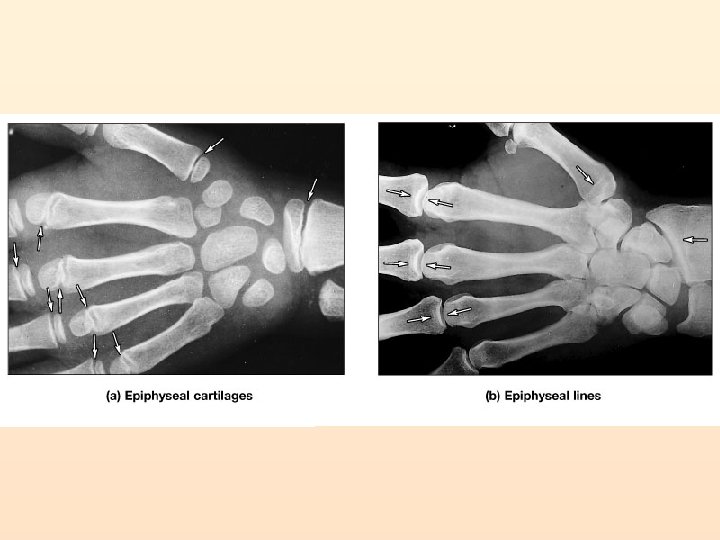

2 Types of Ossification 1. Intramembranous Ossification Mesoderm Mesenchymal cells Osteoprogenitor cells Osteoblast Osteocytes in bone tissue

2. ENDOCHONRAL OSSIFICATION starts as a cartilage model of bone

Appositional Bone Growth Bone Remodeling: Depositing and removing bone tissue!